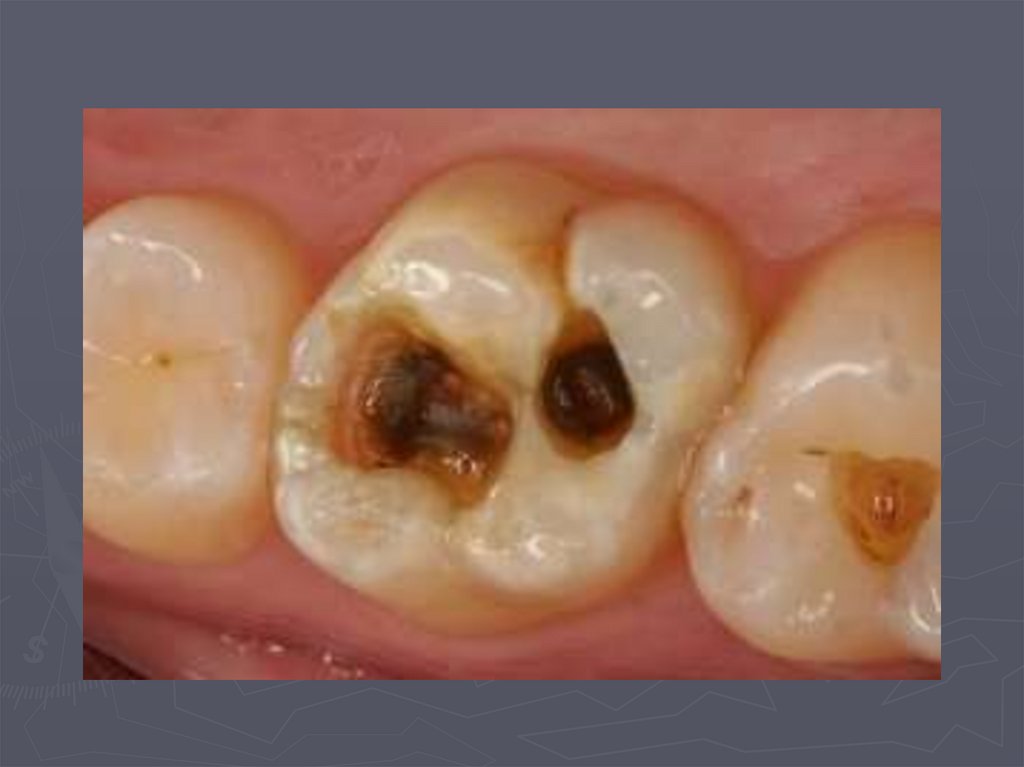

38. КЛИНИЧЕСКАЯ КАРТИНА СРЕДНЕГО КАРИЕСА при декомпенсированной форме:

► при локализации кариозной полости в фиссурах

определяется небольшое входное отверстие;

► при раскрытии обнаруживается кариозная

полость с податливым дентином;

► края кариозной полости нависают;

► эмаль тонкая, хрупкая;

► дентин светлый, влажный, размягченный, легко

удаляется экскаватором;

► зондирование болезненно по

эмалево-дентинному соединению.